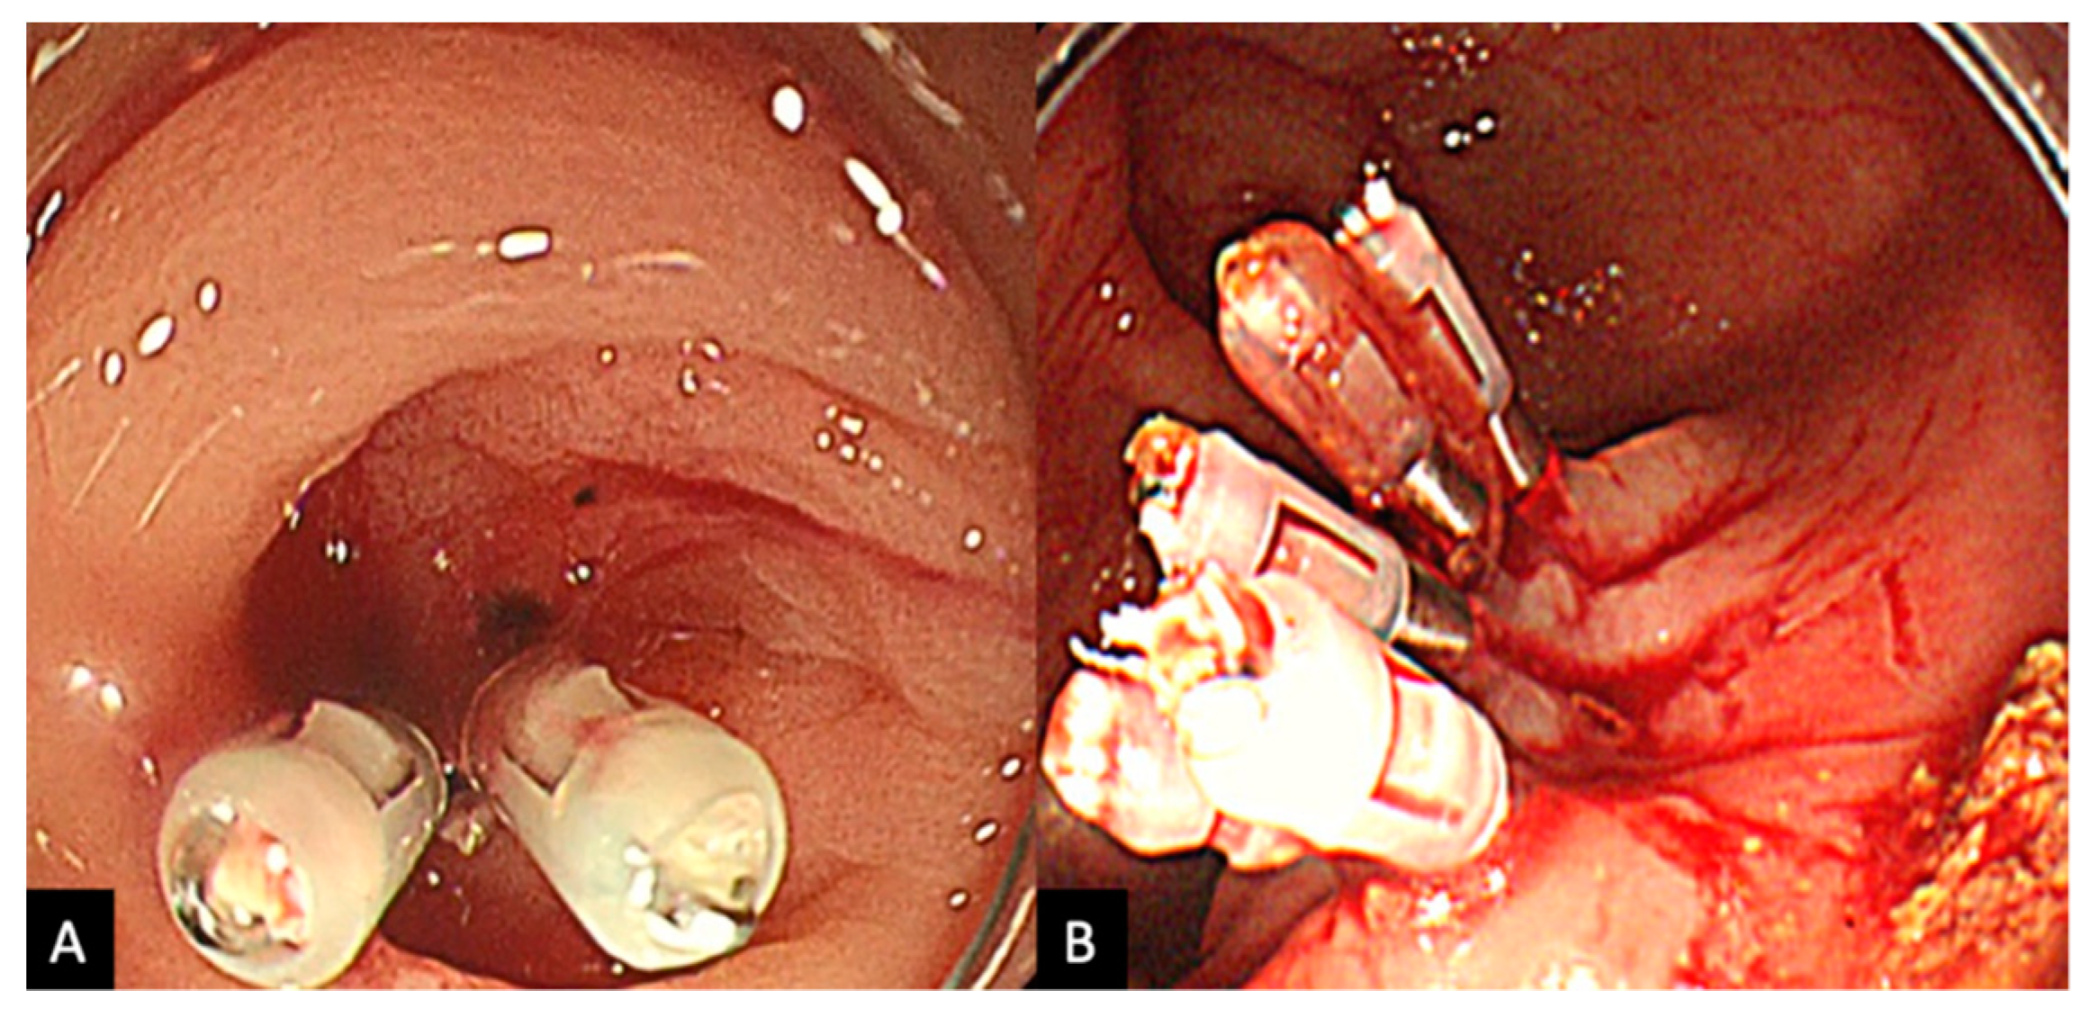

2.2. Procedure